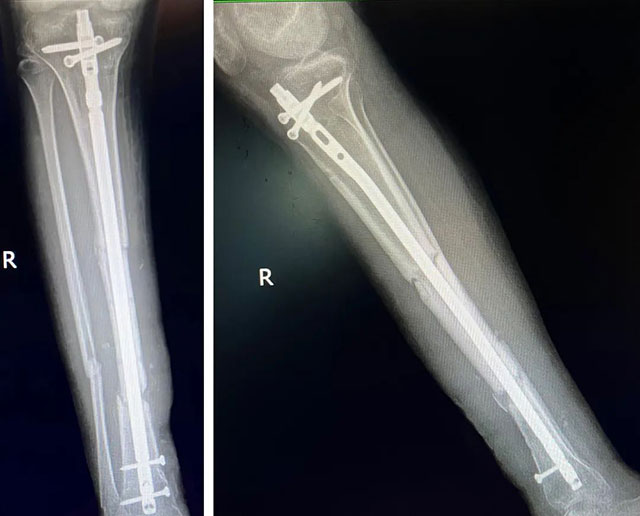

7月4日,骨伤科创伤·正骨组黄陈翼副教授为小徐实施了三期手术:骨折内固定手术。预计3-6个月,骨折愈合,小徐便可恢复行走。